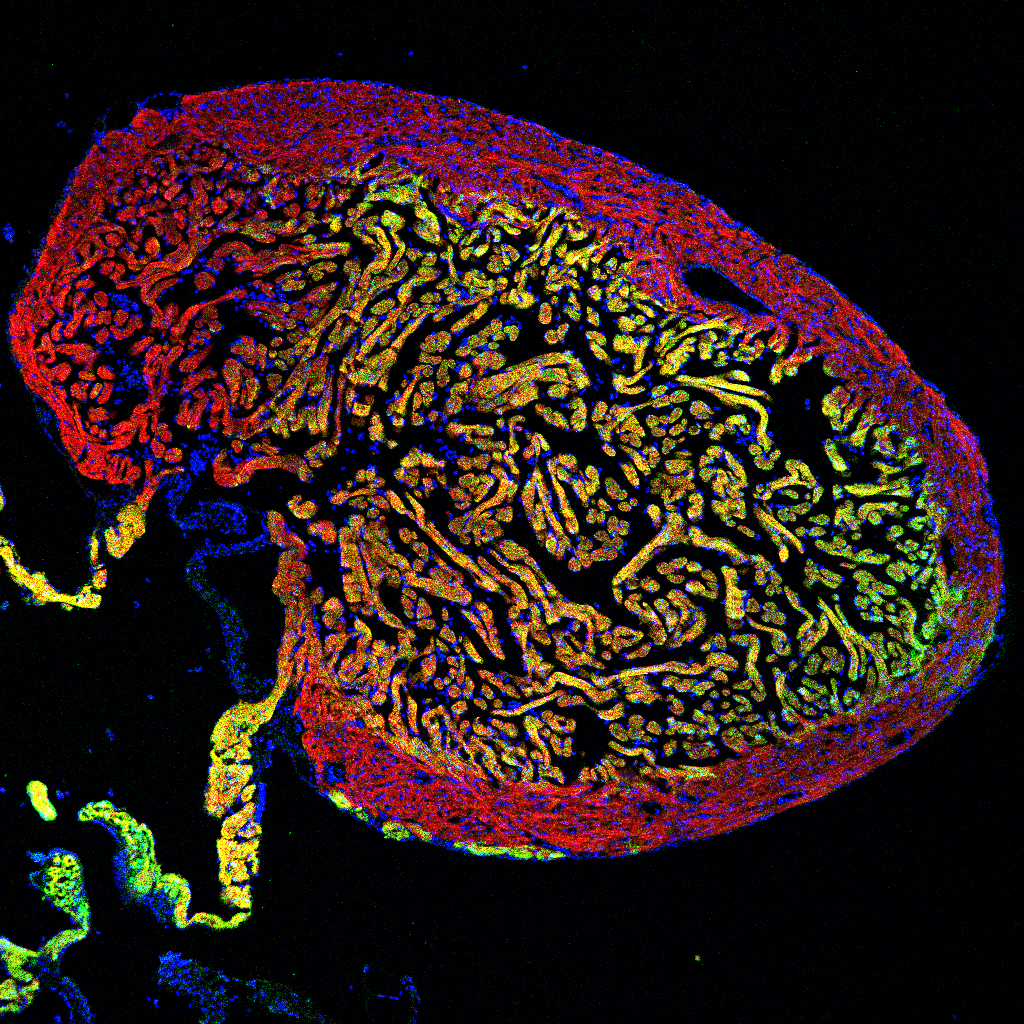

Ein Team um Dr. Nadia Mercader am Institut für Anatomie der Universität Bern konnte nun in enger Zusammenarbeit mit Mitarbeitern am Forschungsinstitut CNIC in Madrid (Spanien) und der Gruppe von Dr. Christian Mosimann an der Universität Zürich zeigen, dass Herzmuskelzellen des Zebrafisches höchst flexibel sind. Die regenerierenden Herzmuskelzellen können sich im ausgewachsenen Herzen anpassen, um den Zellen in den verschiedenen Regionen der vormals defekten Herzwand zu ähneln. Doch können im Zebrafisch Herzmuskelzellen aus allen Teilen des Herzens bei der Reparatur helfen? Um dies zu beantworten, schaute sich das Team auch die Frühentwicklung des Herzens an.

Die Studie des Teams um Dr. Mercader zeigt nun, dass bereits bei der frühen Herzentwicklung ein hoher Grad an Plastizität vorhanden ist: wenn Muskelzellen des anfänglichen Herzschlauches zerstört werden, übernehmen die später hinzukommenden Zellen die ursprüngliche Funktion, trotz ihrer eigentlich anderen anfänglichen Aufgabenstellung.